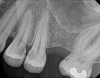

(2.) Postoperative radiograph after the performance of nonsurgical root canal re-treatment on tooth No. 30 and root canal therapy with hydraulic condensation and bioceramic sealer on both teeth followed by amalgam core buildups. (Case courtesy of David Tran, DMD, Advanced Graduate Program in Endodontics, Harvard School of Dental Medicine).

Figure 2